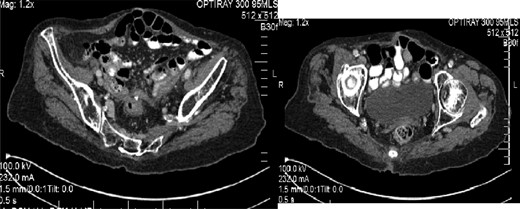

Following discharge, the patient re-presented to the clinic 2 years later complaining of increasing discharge from her rectal stump with a simultaneous decrease in colostomy output. A sigmoidoscopy demonstrated two fistulae within the rectal stump, and a CT confirmed a communication between the stump and proximal small bowel (Fig. 2). She has elected for conservative management of her condition.